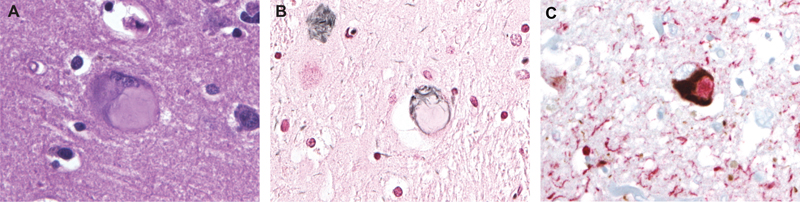

Figure 14. Composite neuronal tau inclusion (CNTI) in a family with a P136S mutation in MAPT. A. H&E, B. Gallyas silver staining displays only the peripheral part of the inclusion, which is 4RTau positive, while the central part is only 3RTau positive in double immunohistochemistry on 3R and 4R Tau (in C).

I recognized that this mutant tau produced in all affected family members a new neuronal tau inclusion consisting of two components (Figure 14). We designated it Composite Neuronal Tau Inclusion (CNTI) [22]. Additionally, I discovered that in one family member’s brain, in addition to CNTI, all other neuronal tau inclusions known so far were present [23].